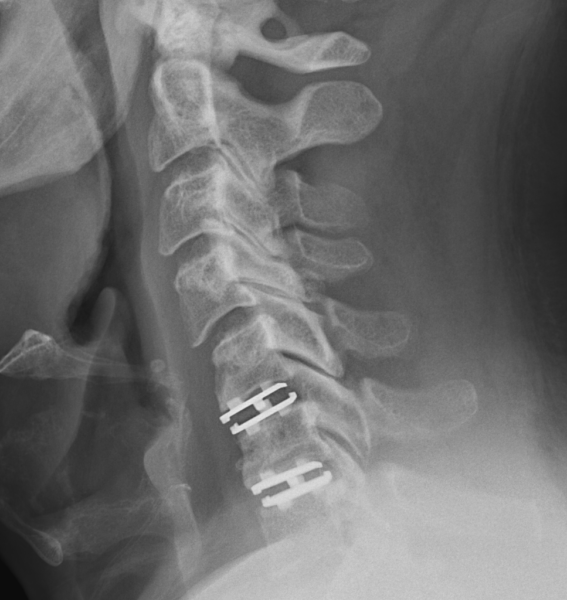

Le Dr Éric Truffer, MD, FRCSC, offre des services spécialisés en neurochirurgie, principalement orientés vers le traitement des pathologies de la colonne vertébrale et des nerfs périphériques.

Toutes les chirurgies de la colonne vertébrale sont effectuées à l’aide du microscope, une méthode éprouvée qui permet d’optimiser les résultats tout en minimisant les risques et les complications.

Domaines d’expertise

Colonne lombaire